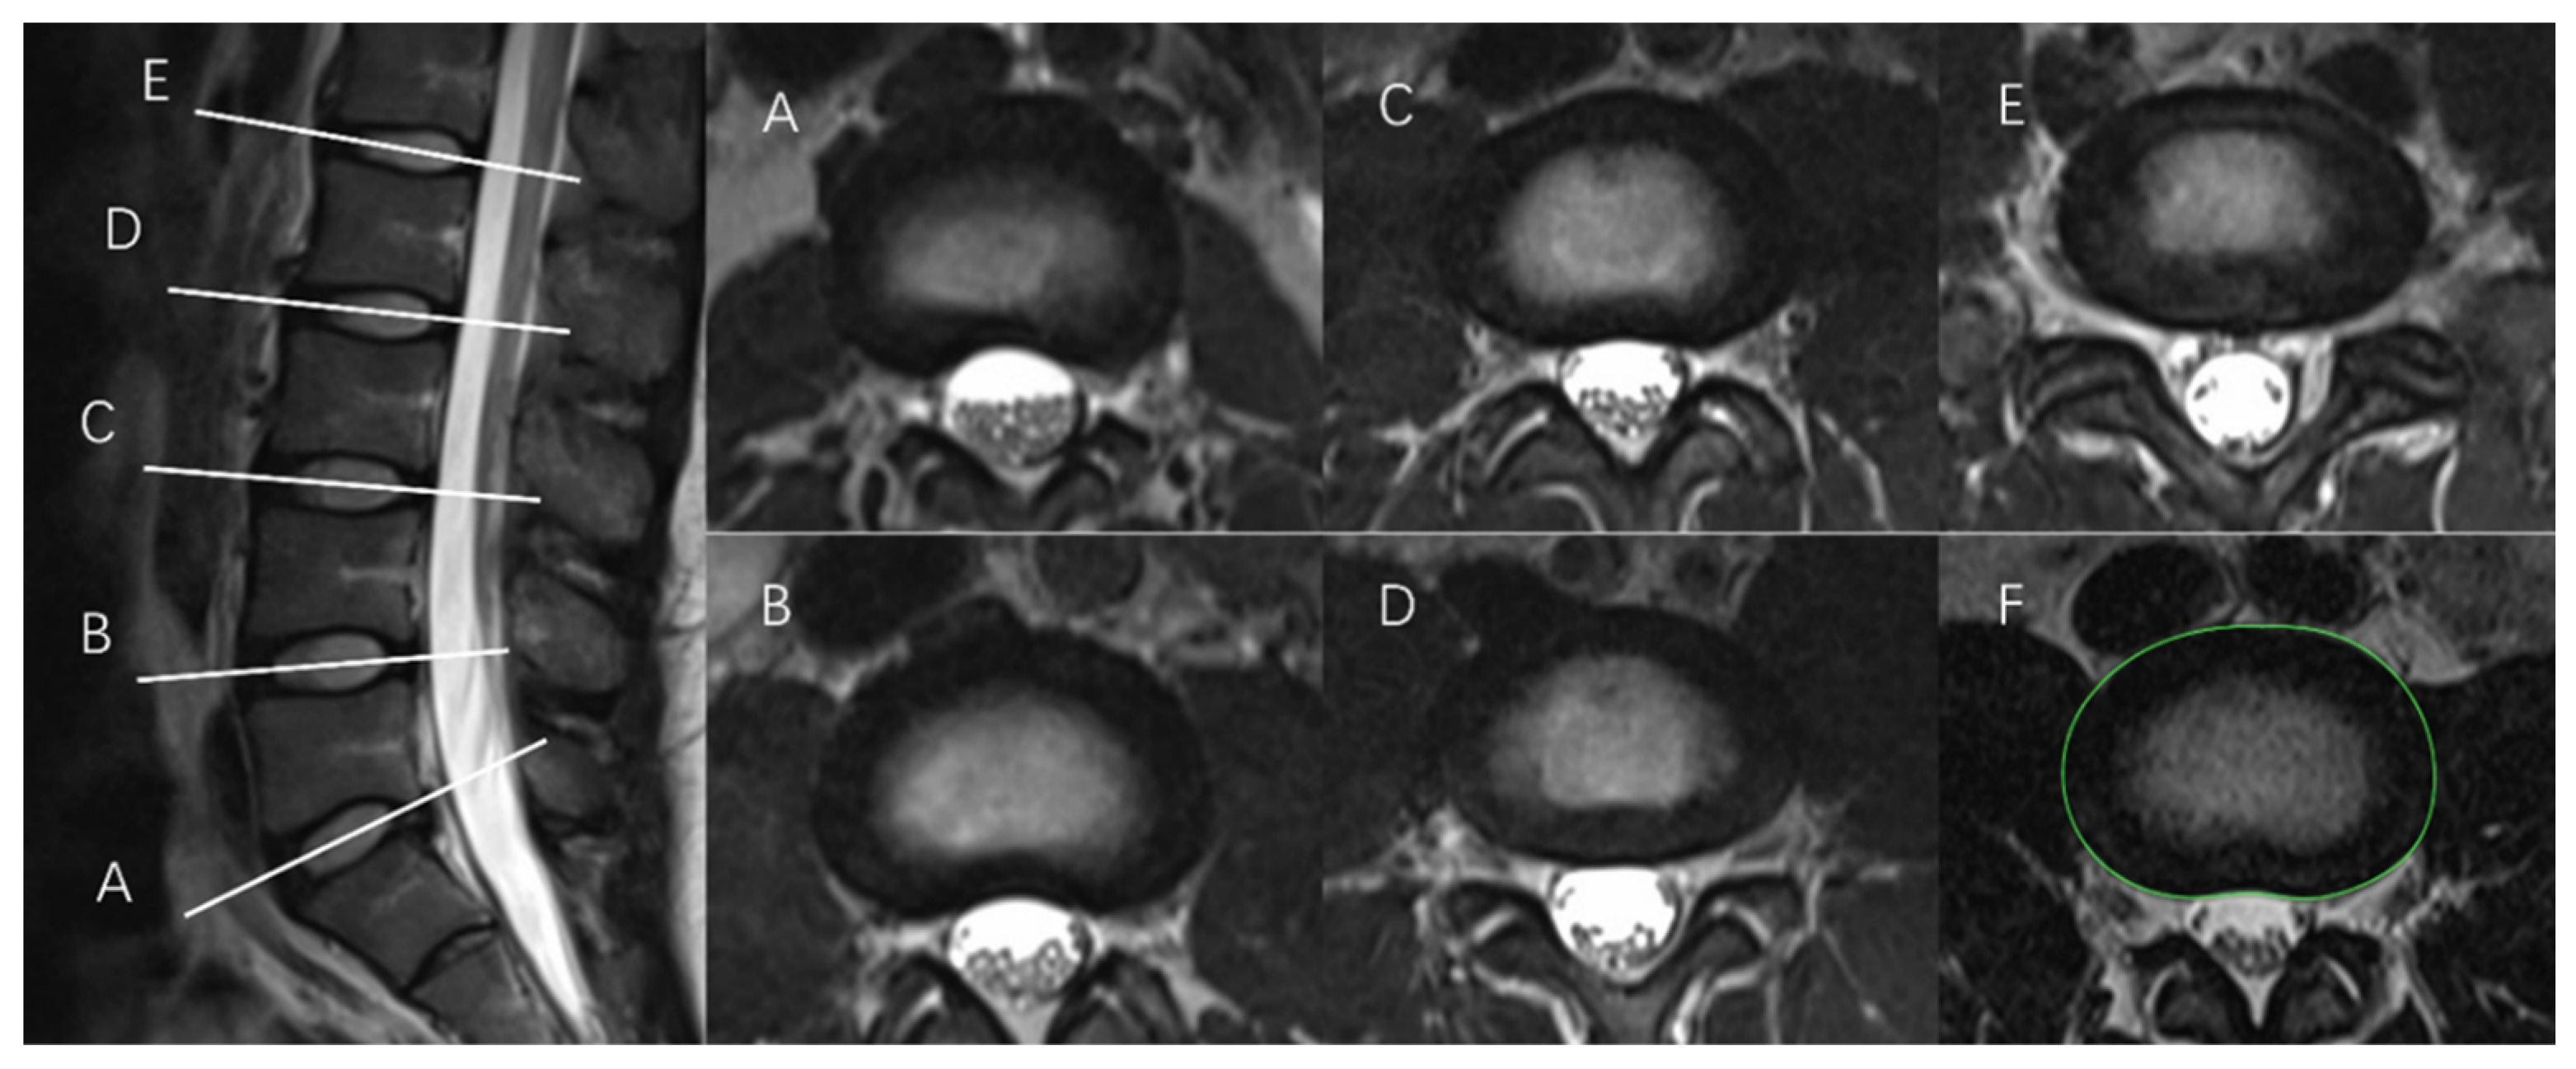

2.2. Measurement of IVD Structures

2.2.1. Tracing the IVD Contours

2.2.2. Tracing the NP Contours

- Manual tracing (MT)

2.3. Determination of NP-to-CSA Ratios